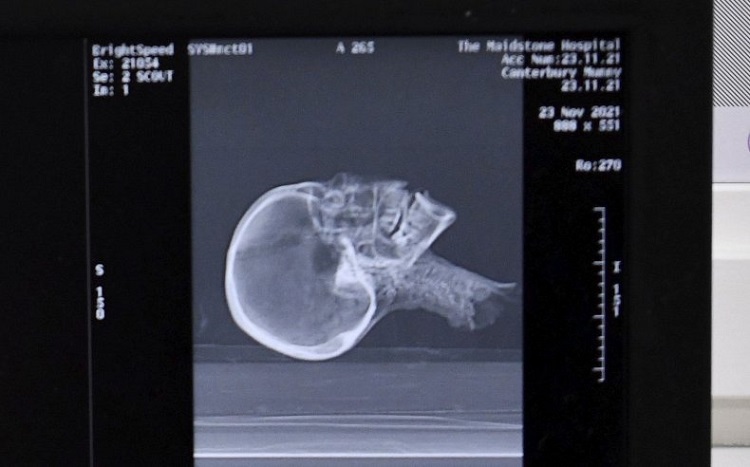

این سر مومیایی شده برای بررسیهای بیشتر به موزه و دانشگاه کانتربری سپرده میشود تا اطلاعاتی در خصوص هویت و منشاء آن بدست آید. در ابتدا این سر مومیایی شده تحت آزمایش اشعه ایکس قرار گرفت و مشخص شد که سر متعلق به یک زن بالغ است، اما برای تأیید و کسب اطلاعات بیشتر تصویربرداری سی تی اسکن نیز لازم بود. به گفته محققان، نتایج اولیه سی تی اسکن، که در بیمارستان Maidstone انجام شد، نشان داد که این زن در حدود ۲۰۰۰ سال پیش سربریده شده و خاستگاه آن نیز از مصر باستان بوده است.